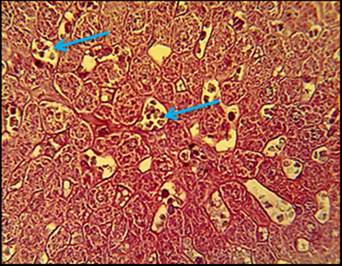

In addition, a marked fibrosis was found to be replacing hepatocytes with congested dilated of sinusoids (fig. 3).

Fig. 3: Histopathological section in liver of animal administration with cholesterol showed marked fibrosis replacement of hepatocytes (red arrow) with congested dilated of sinusoids (blue arrow), (H and E stain 40X)